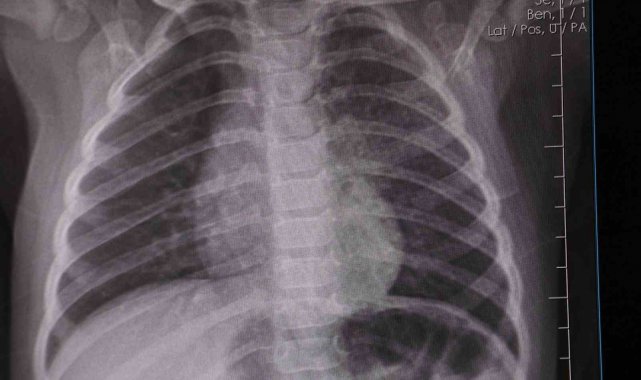

Dr. Tuğçe Uçar, influenzanın her yıl kış mevsiminde daha yaygın hale gelen ve solunum yolu enfeksiyonlarına neden olan bir virüs olduğunu belirterek, "İnfluenza, her yıl kış mevsiminde daha yaygın hale gelen ve solunum yolu enfeksiyonlarına neden olan bir virüstür. Çocuklarda yüksek ateş, öksürük, burun akıntısı, yaygın kas ağrıları, halsizlik ve genel vücut yorgunluğu gibi şikâyetlerle kendini gösteren bir hastalık tablosuna yol açar. Özellikle kreş ve okul çağındaki çocuklarda çok hızlı yayılır. Solunum yoluyla, damlacık enfeksiyonu şeklinde bulaşır. Bu yüzden, ellerin düzenli olarak yıkanması, kalabalık ortamlardan uzak durulması ve hijyen kurallarına dikkat edilmesi büyük önem taşır. Hasta bireyden bulaştıktan sonra belirtiler genellikle ilk 24 saat içinde ortaya çıkmaya başlar. Hastalık ortalama 7-10 gün sürer. Ateşli dönem ise genellikle 5 gün kadar devam edebilir. Öksürük ise birkaç gün içinde başlayıp birkaç haftaya kadar devam edebilir" dedi.

Dr. Uçar, influenza hastalığının kalıcı bir bağışıklık bırakmadığını söyleyerek, "Hastalığın tanısını çoğu zaman kan tahliline gerek kalmadan, burundan alınan sürüntü örnekleri ile koyabiliyoruz. Erken tanı konulursa, hastalığın mümkün olan antiviral tedavisine erken başlayabiliyoruz. Böylelikle gelişebilecek akciğer komplikasyonları gibi ciddi riskleri azaltmış oluyoruz. İnfluenza hastalığı ne yazık ki kalıcı bir bağışıklık bırakmıyor. Domuz gribi, kuş gribi olarak bildiğimiz H1N1 virüsü, çeşitli mutasyonlara uğrayarak her yıl değişik varyantlarla karşımıza çıkıyor. Bu hastalığı bir kere geçirmek bir daha geçirilmeyecek anlamına gelmiyor. Özellikle ekim ve nisan ayları arasında pik yapan bu hastalığın bir aşısı mevcut. İnfluenzadan korunmak için riskli gruplara da aşılanmayı öneriyoruz" diye konuştu.